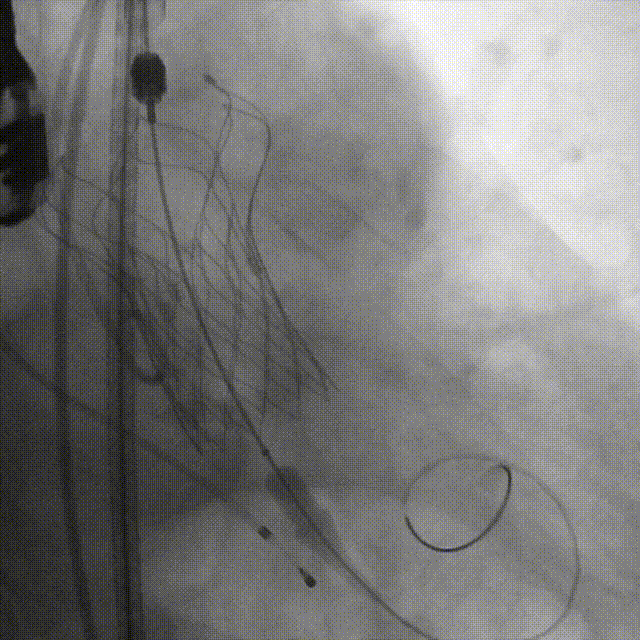

导丝跨瓣

瓣膜定位,0位释放

释放2/3处造影确认植入深度

释放瓣膜